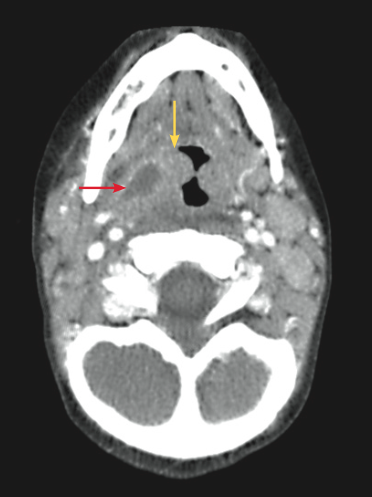

Alexander C. Arroyo, MD; Alexander K.C. Leung, MD, MBBS, FRCPC, FRCP; Kael Duprey, MD, JD; Marisa Vermeulen, DO

A 23-day-old boy born at 39 weeks’ gestation via normal spontaneous vaginal delivery was brought to the emergency department with vomiting of 1 week’s duration.